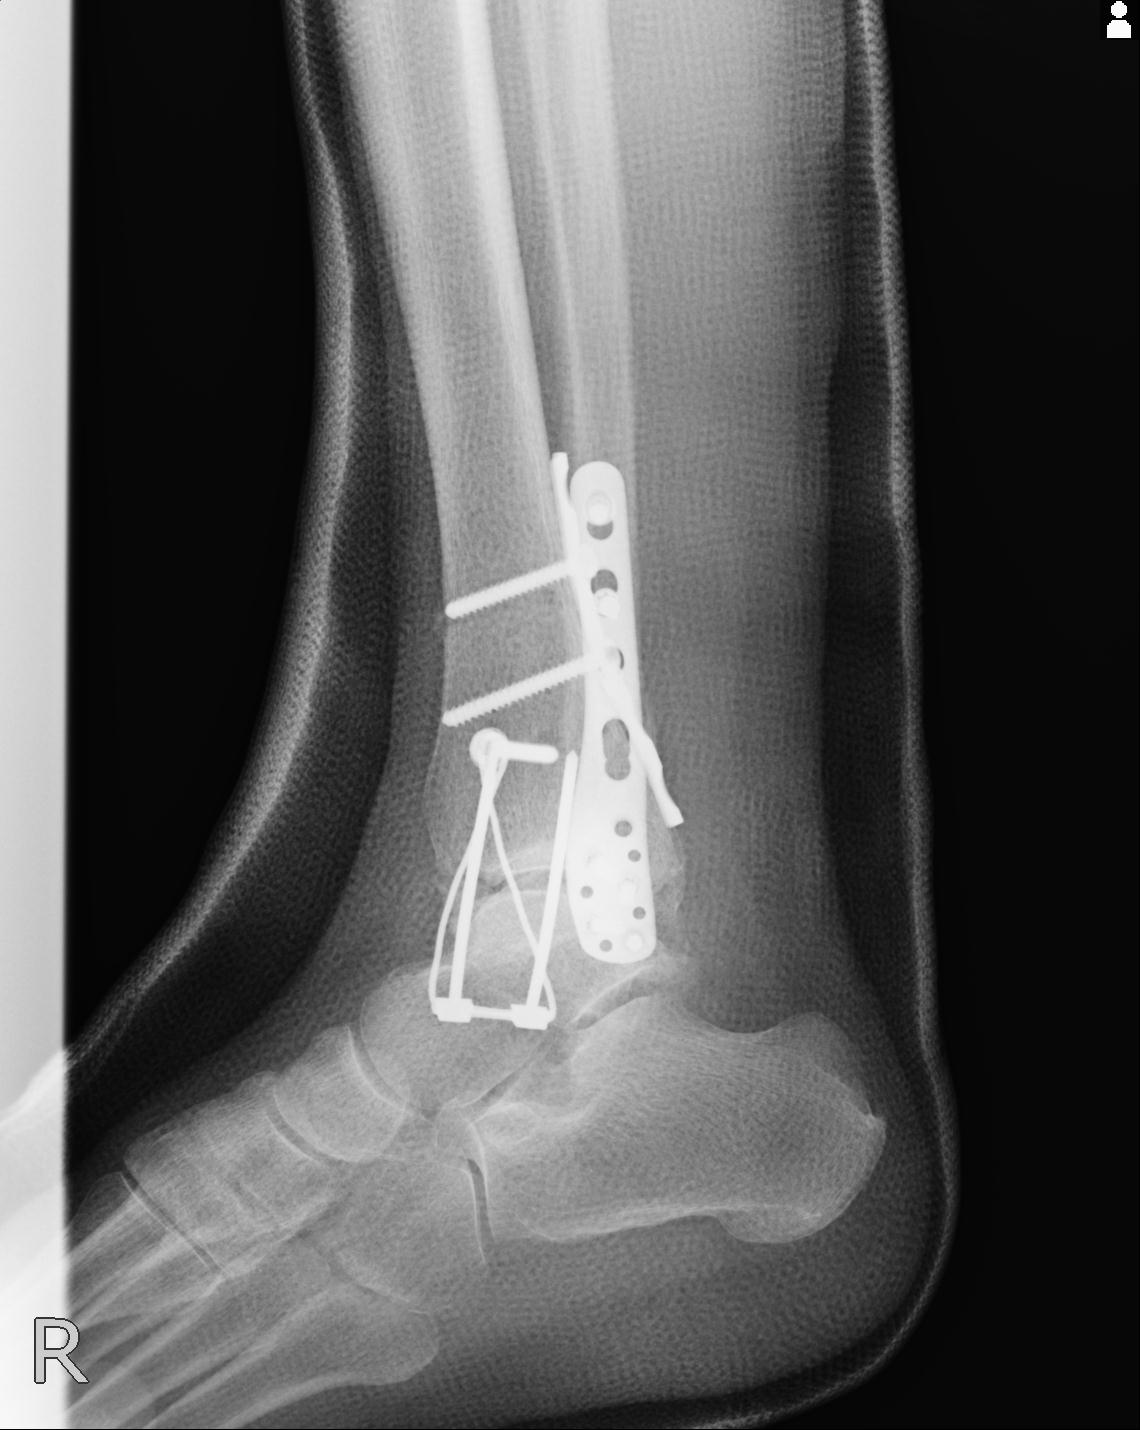

102755 1/4 2R 1/15 2R 右足関節 68歳女性 右三果脱臼骨折